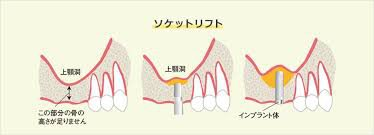

ソケットリフト

ソケットリフトとは、上顎洞底挙上術と呼ばれています。上顎骨の再生手術のひとつです。口の中から、上顎洞の底を持ち上げて、インプラントの埋入に必要なスペースを確保する処置になります。上顎洞の形には、個人差があり必ず必要な処置ではありませんが、感染により上顎骨の吸収が大きい場合は、人工骨や自家骨の補填では十分なスペースが確保できない場合に行います。

ソケットリフトの術式

口腔内の当該部位の歯肉を切開します。その後、骨を上顎洞近くまで削っていきます。この際、削る量や深さは、事前にCTにて計算しておきます。その後、オステオトームと呼ばれる先端がノミのようになった器具で上顎洞まで進めていきます。オステオトームには、ストッパーがついていますので安全に処置することが可能です。その後、必要に応じて、骨補填材を使用して、上顎洞内の粘膜を挙上していきます。インプラントを同時に埋入する場合がほとんどです。粘膜の挙上する大きさによっては、適応にならないことがあります。一般的には、浸潤麻酔のみで処置しますが、静脈内鎮静法や笑気麻酔を併用することも可能です。